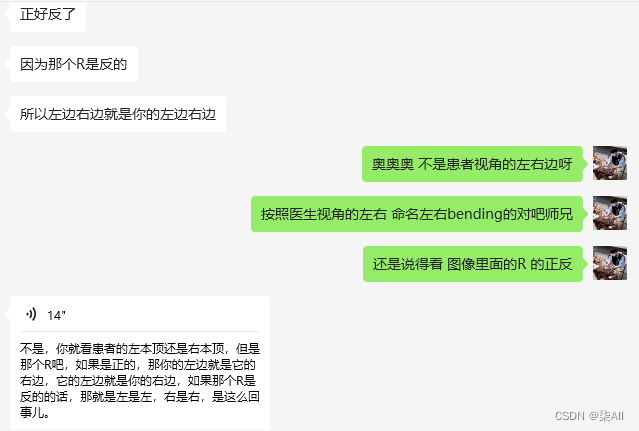

脊柱数据有四方位的数据,冠状位、矢状位、左bendin、右bending

2、需要标注的关键点(冠状位、左右bending位)

冠状位(一共是标记72个关键点)

左右bending(一共也是标记72个关键点)